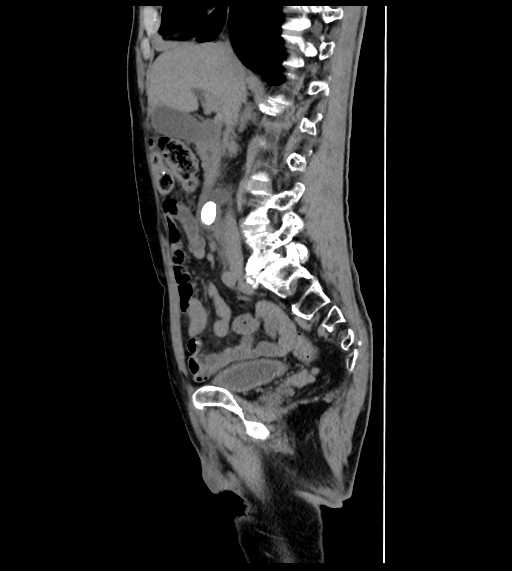

腹部

尿管結石

胆石

脂肪肝